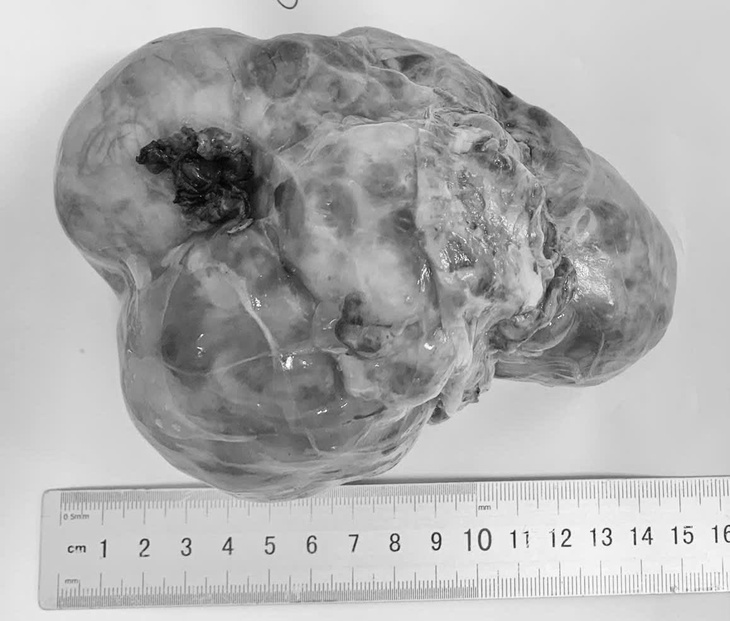

Theo khoa ngoại Bệnh viện Phụ sản - Nhi Đà Nẵng, ba bệnh nhi vừa được phẫu thuật gồm trẻ 14 tháng tuổi mắc u nguyên bào thận (Wilms), trẻ 4 tuổi mắc u nguyên bào thần kinh, trẻ 5 tháng tuổi mắc u quái ổ bụng cùng quê Quảng Ngãi. Đây đều là những khối u có thể gặp ở trẻ em, trong đó có loại ác tính và nguy cơ tiến triển nhanh.

Đáng chú ý, các trường hợp này đều được phát hiện khi khối u đã lớn, gây khó khăn cho điều trị và làm tăng nguy cơ biến chứng.

Các bệnh nhi được phát hiện khi khối u đã lớn - Ảnh: T.H.